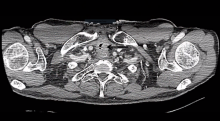

A 61-year-old man was treated for laryngeal squamous cell cancer with radiation in 2004. He presented again in 2012, with squamous cell cancer on the floor of his mouth. He underwent a right mandibulectomy with a free forearm flap, followed by radiation. A year later, he was found to have recurrent laryngeal cancer and underwent a total laryngectomy. Unfortunately, one of the margins was positive on the final pathology. The patient presented again in 2013 with obstructive symptoms and hemoptysis, synonymous with local recurrence at the tracheostomy level. There was no evidence of distant disease, and, in view of his relative young age and good functional status, he underwent a mediastinal tracheostomy with a right myocutaneous pectoralis flap.

The patient's postoperative course was significant for moderate ischemia of the proximal posterior tracheal wall. This was managed conservatively, with the patient requiring multiple dilations and the temporary placement of a fully covered airway stent, before tolerating a permanent laryngeal tube. Pathological examination showed all the new margins to be negative, and multiple subsequent imaging studies revealed no local recurrence. However, the patient was found to have a suspicious 1 cm left upper nodule for which he underwent a thoracoscopic wedge resection 22 months after his mediastinal tracheostomy. This showed another squamous cell cancer that was less differentiated than his prior oral and laryngeal cancers. The patient is currently disease free, 36 months after his mediastinal tracheostomy.